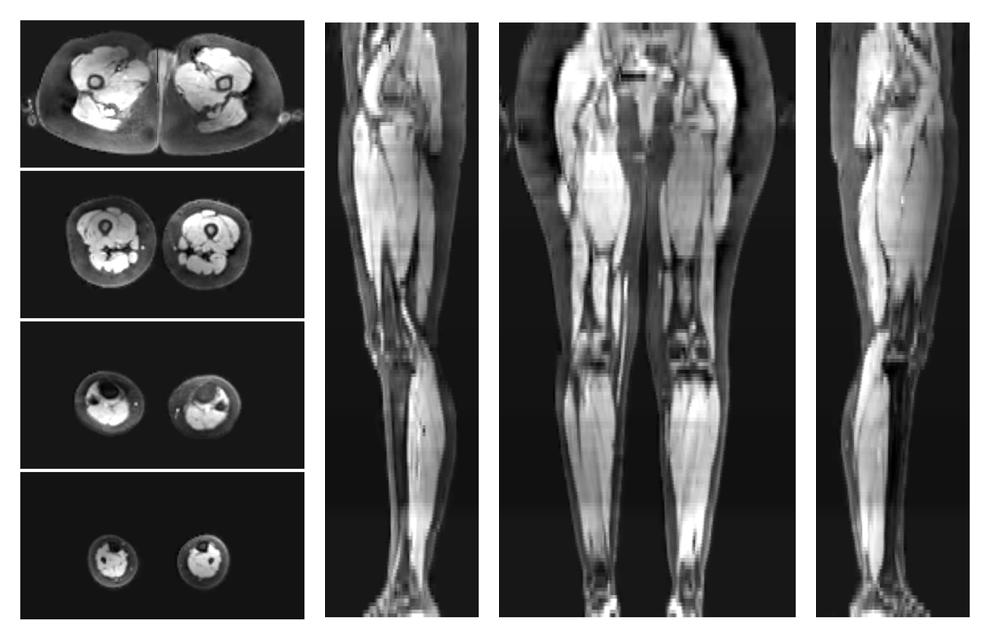

• Automated muscle and bone segmentation.

Overlay of automated muscle segmentation labels on dixon water image.